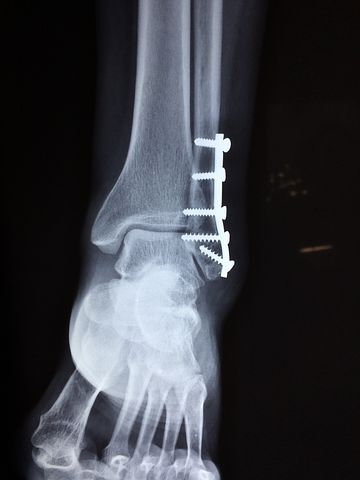

관절의 염증이 장기화되어 관절을 쓸수없게 되면, 인공 관절로 대체 수술이 필요할수도 있습니다.